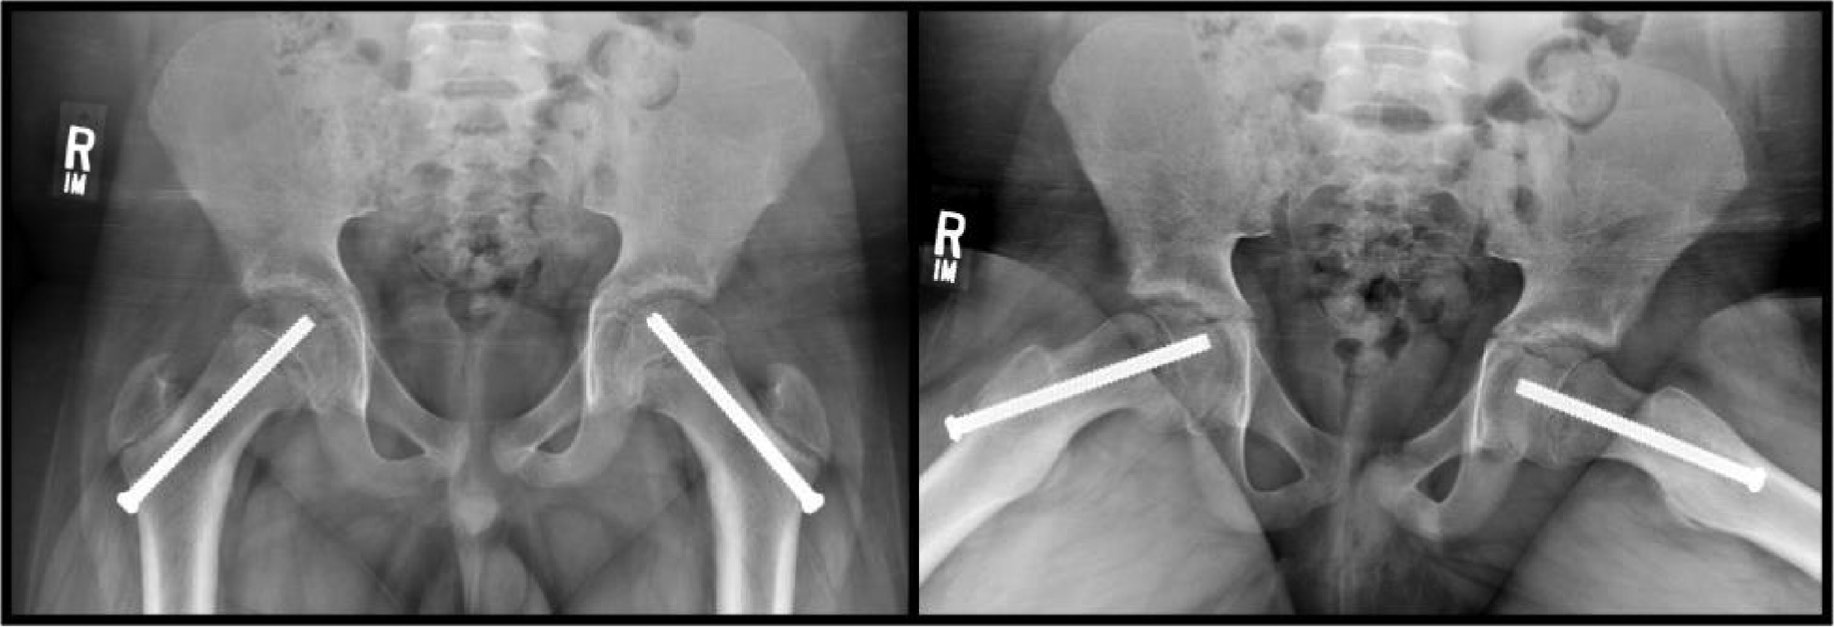

In situ fixation is the gold standard for the treatment of stable SCFE. Current standards for in situ pinning (ISP) of a stable SCFE include the placement of one cannulated screw placed perpendicular to the physis, penetrating the epiphysis at the center with at least four screw threads crossing the physis (Figure 4).

Figure 4. Bilateral in situ screw fixation of stable slipped capital femoral epiphysis. Note the central position of the screw on the AP and lateral views with at least four screw threads in the epiphysis.

Additionally, to prevent penetration into the joint space, the findings from Senthi et al.43 recommend a distance of at least 5 mm from the subchondral bone on all views. ISP effectively makes no overt attempt to correct the presenting deformity but focuses on preventing additional slip and subsequent deformity instead. A serendipitous reduction may be achieved during patient positioning with internal rotation of the hip to position the patella directly up. Napora et al.44 acknowledged that this serendipitous reduction can be performed purposefully without increased rates of AVN in unstable SCFE. However, forceful reduction is not performed to avoid iatrogenic displacement that may injure the retinacular vessels supplying the epiphysis.

Similarly, the gold standard for management of unstable SCFE remains ISP. In contrast to stable SCFE, unstable SCFE is generally treated in an urgent fashion similar to a transphyseal femoral neck fracture. Treatment is also unique from management of stable SCFE with the addition of 1) placement of two screws rather than a single screw, 2) the addition of capsulotomy to address possible intracapsular hematoma, and 3) monitoring of capital femoral epiphyseal perfusion.